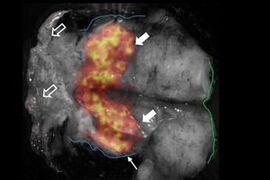

Lightpoint Medical molecular imaging aids prostate surgery

Dutch clinical trial and support from UK's RAE both indicate potential impact of Cerenkov luminescence imaging.